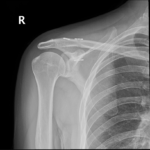

- Shoulder Fractures.

- Clavicle Fractures.